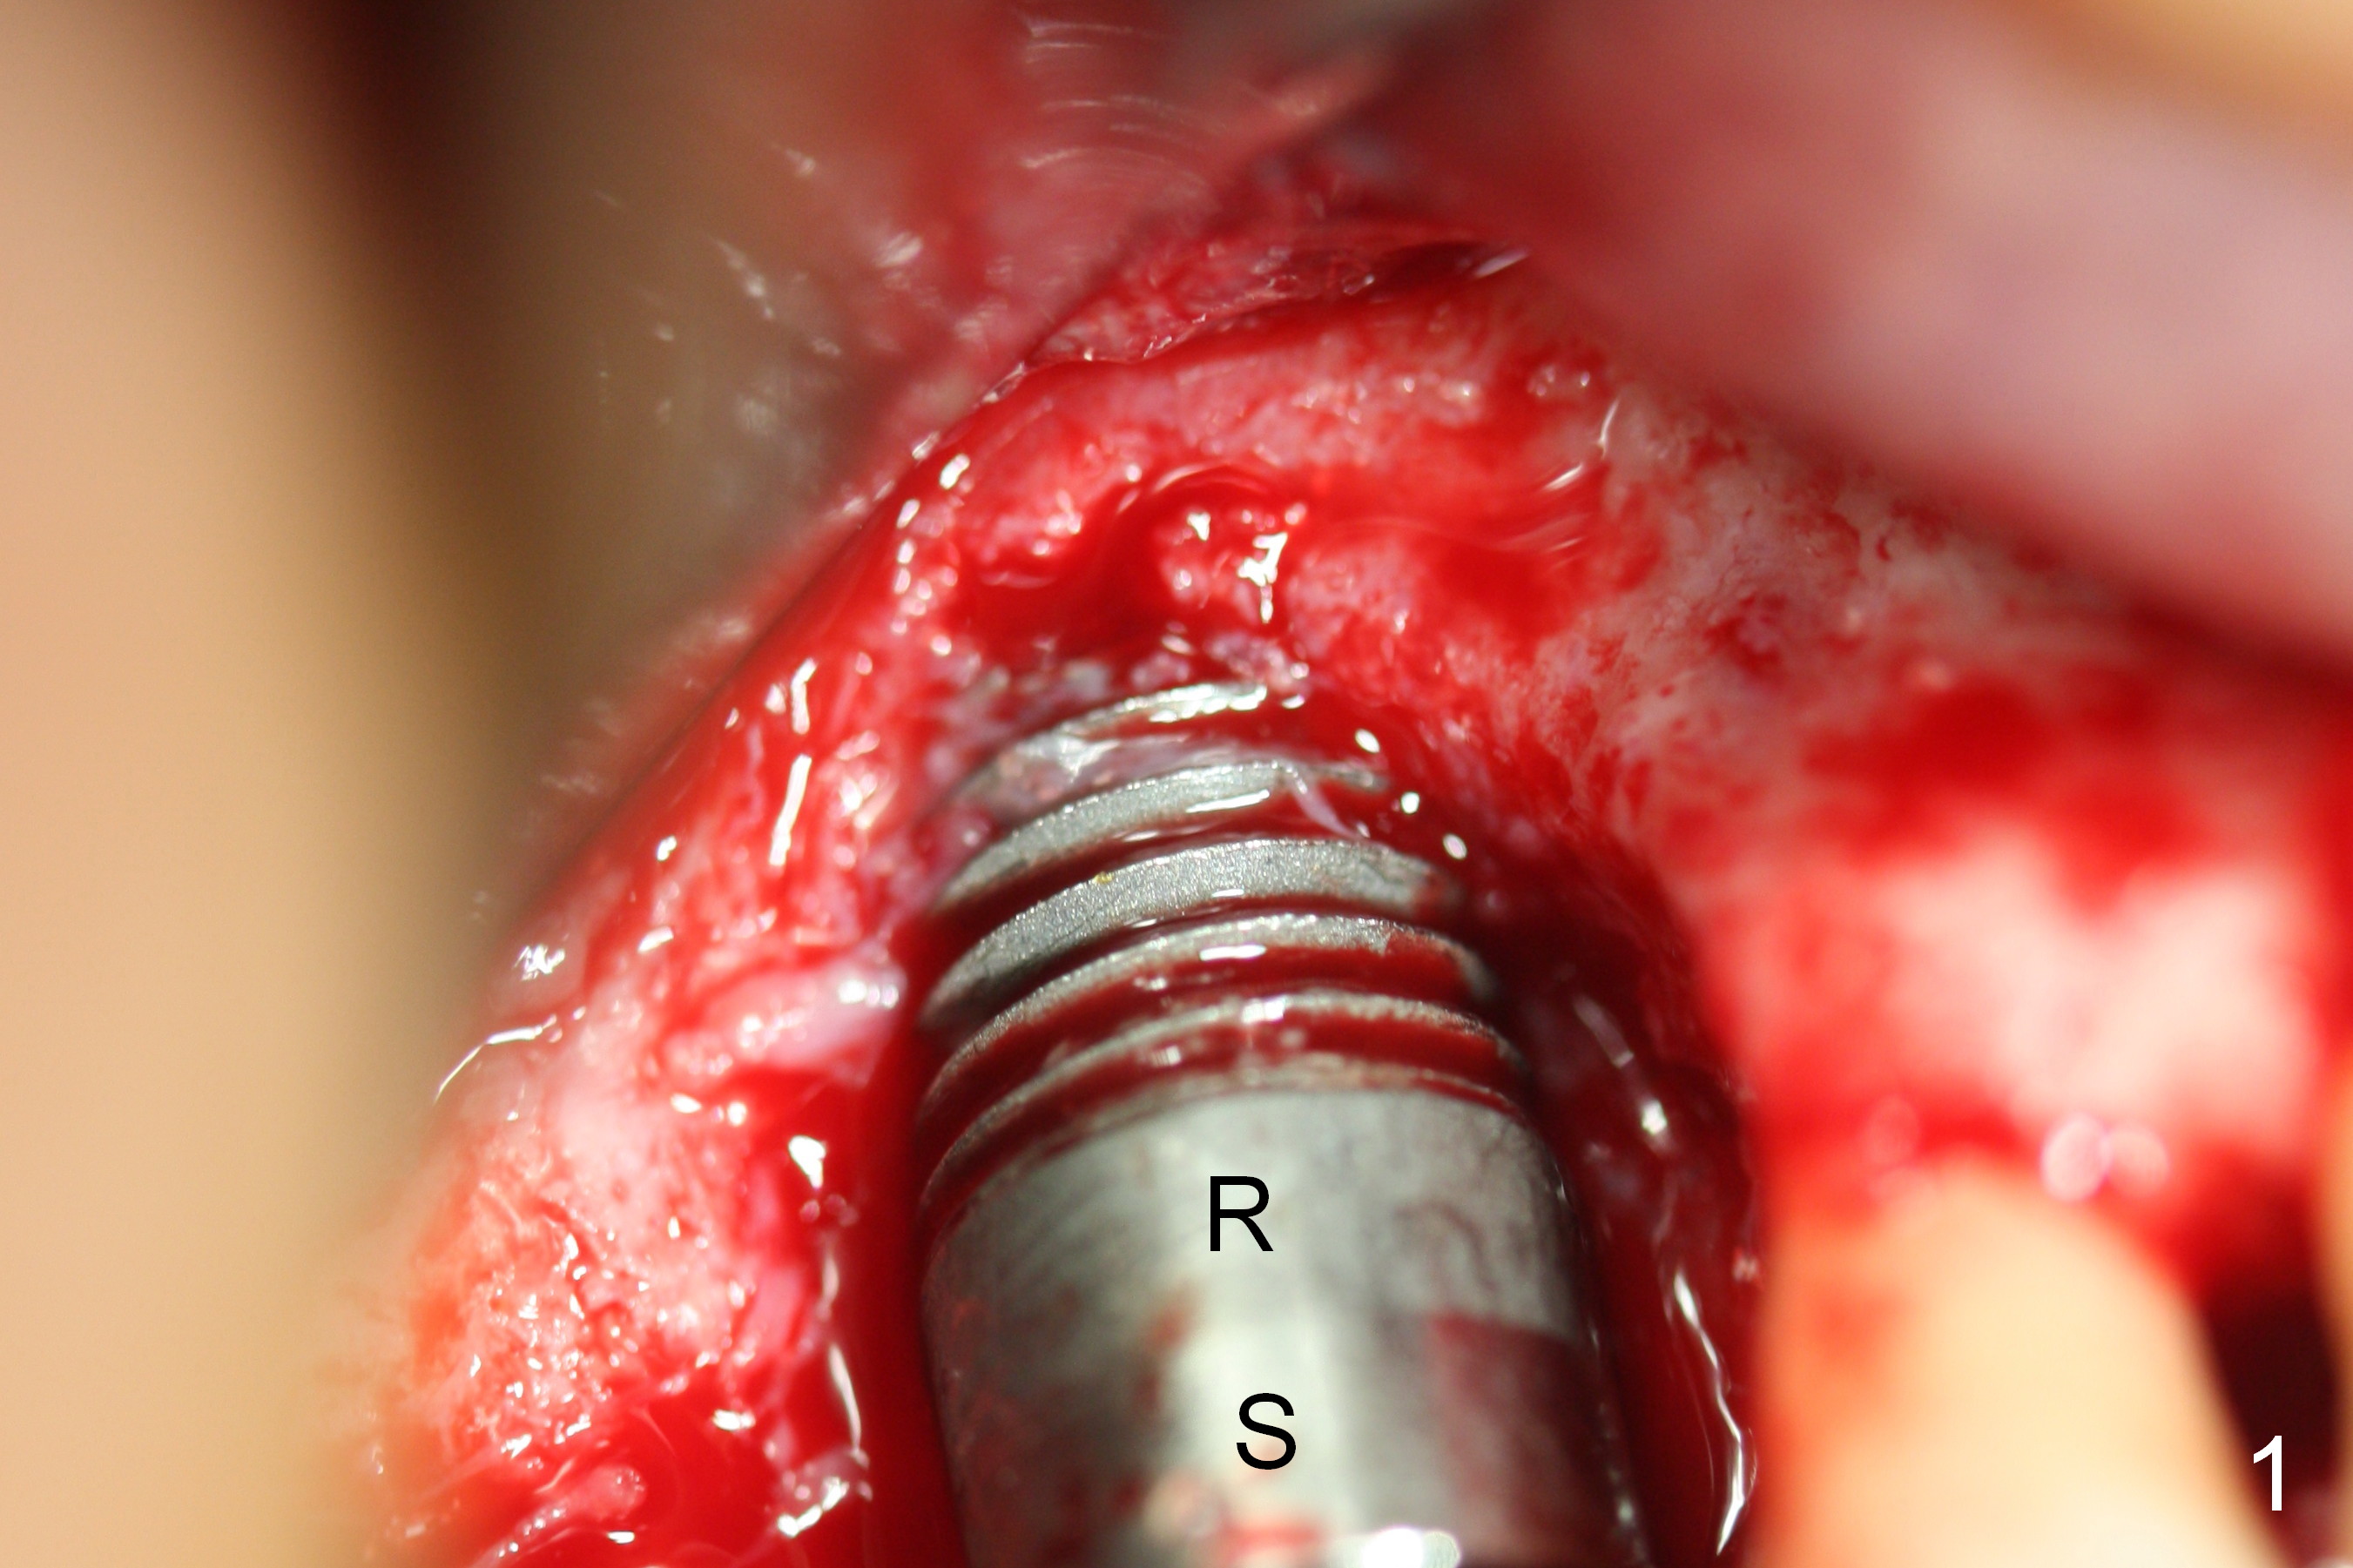

Three months post 1st GBR, a larger flap is raised to reveal a seemingly large bony defect around the exposed threads (Fig.1). After thorough debridement, the threads are treated by Clindamycin soaking, Chlorhexidine, Hydrogen Peroxide and EDTA rubbing. Autogenous bone is harvested from the tuberosity. The tooth #2 with mobility II is extracted. The autogenous bone graft is placed over the exposed thread, supplemented by Osteogen in syringe. The graft is fixed by a Titanium mesh. An abutment is placed to keep perio dressing in place. Post op, the patient is doing well. The perio dressing is dislodged 2 weeks postop.